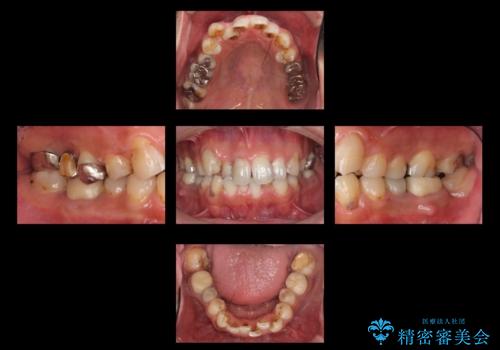

短期間で歯並びをきれいにしたい セラミックでかぶせる治療でも良い

- 短期間で歯並びを治したいとのこと。期間が短ければセラミックでかぶせる治療できれいにするのでも構わない。虫歯の治療もすべてお願いしたいとのことでした。

右下の奥歯は残せない可能性を説明しました。

また、歯並びの矯正をするのではなければ、右上の八重歯は、犬歯を抜くか、奥に入っている歯を抜くかになるとお伝えしました。結果、根の長い犬歯を残して右上の前歯を抜歯しブリッジにしました。また、前歯の神経は極力取らないで治療を行いました。(結果神経を取る治療は前歯には行っておりません)

右下奥歯二本はインプラントにしました。(横浜桜木町歯科院長 大元先生による)

また、銀歯はすべてやり直しを行い、セラミックでやり替えを行いました。